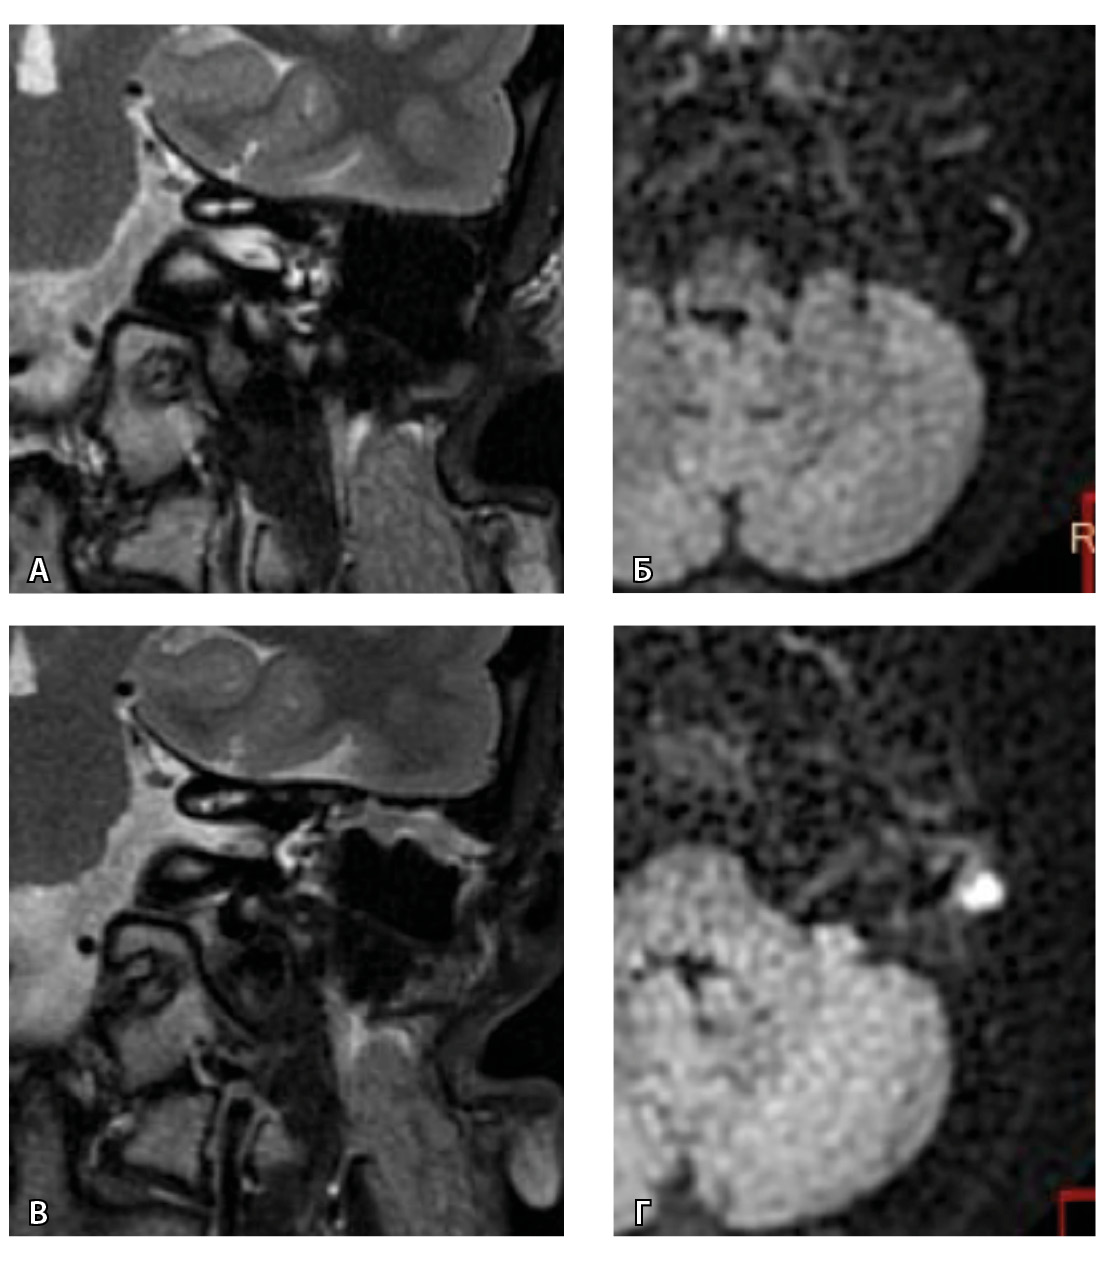

Одним из интересных встреченных нами случаев ложноположительных МР-результатов было грибковое поражение послеоперационной полости с отрицательной динамикой в течение 16 месяцев (рис. 5).

Рис. 5. При первичном послеоперационном исследовании на Т2-взвешенных изображениях во фронтальной плоскости определяется пневматизированная послеоперационная полость (А), без признаков ограничения магнитно-резонансной диффузии (Б). При контрольном исследовании – отрицательная динамика с появлением пристеночных разрастаний вдоль стенок послеоперационной полости (В), ограничивающих магнитно-резонансную диффузию (Г). Данные интерпретированы как рецидив холестеатомы. При оперативном лечении и последующей гистологии – грибковое поражение среднего уха